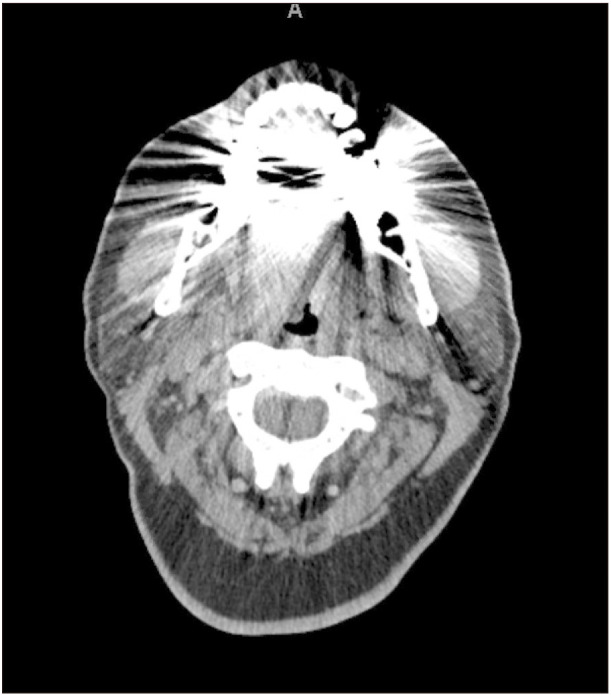

There are very few case reports of the diagnosis and management of concurrent oral cavity and parapharyngeal space tumors. We present a case involving a 49-year-old female who presented with oral cavity squamous cell carcinoma confirmed by biopsy. Initial diagnostic workup revealed a concurrent parapharyngeal mass. Diagnostic studies and surgical therapy were tailored to account for both pathological entities. The patient was treated with a combination of surgery and adjuvant therapy. The surgical strategy was designed to address both lesions simultaneously. One year post-surgery, the patient had good response to therapy with no evidence of persistent or recurrent disease. This report discusses the outcome and treatment of a rare case of concurrent squamous cell carcinoma with a complicating parapharyngeal space tumor. It explores the diagnostic process, comprehensive workup, and the surgical management.